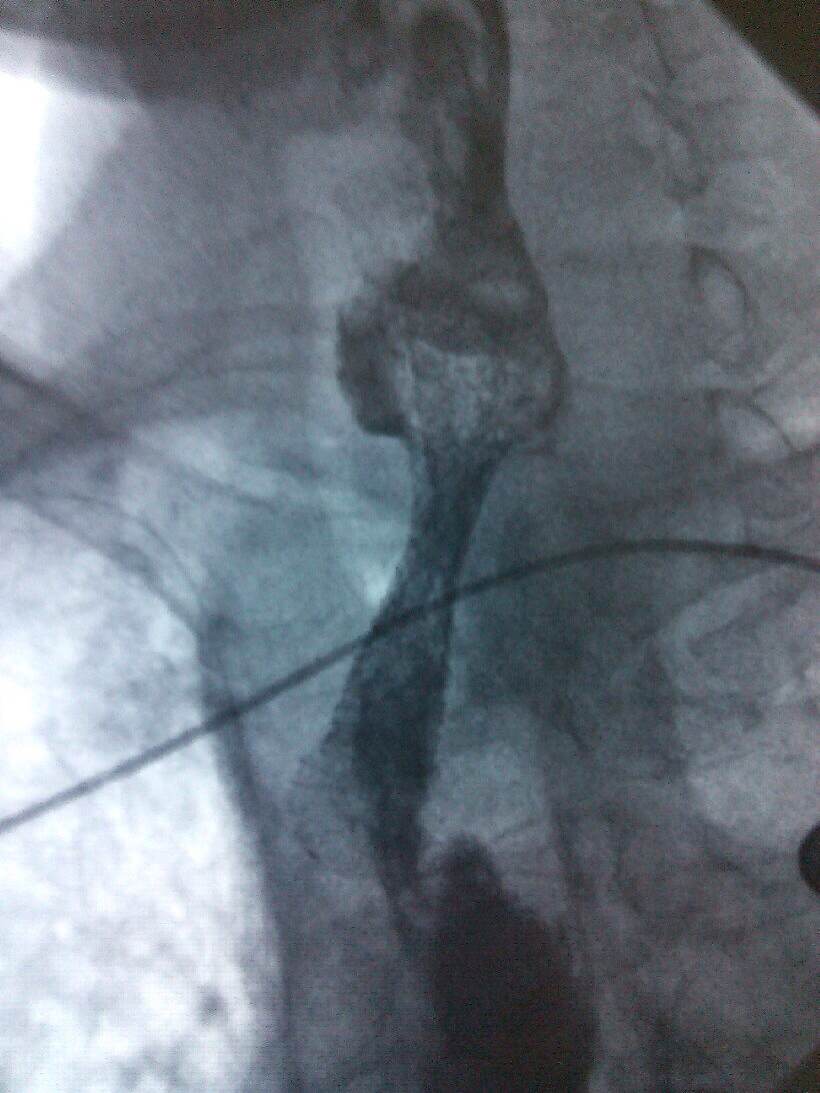

肿瘤科医生仔细检查,该患者肿瘤梗阻的位置高,咽喉及上段食管分泌物无法入胃,经常返流至气管,且分泌物特别多,造成患者非常痛苦,经常夜间被分泌物刺激,咳嗽难忍,无法入睡,造成患者生活质量极差。

根据病人的的身体条件,无法采用手术、放疗、化疗进行治疗。肿瘤科主任、副主任医师熊小平组织医生详细分析患者的病情,找到病因所在,制定周密的治疗方案,运用食管支架植入法将食管扩张,这样既解决了患者的“吃饭”问题,又解决了分泌物排流的问题,减轻了患者的痛苦,提高了生活质量。患者及家属非常感激,多次口头表示感谢:“没想到伦理片